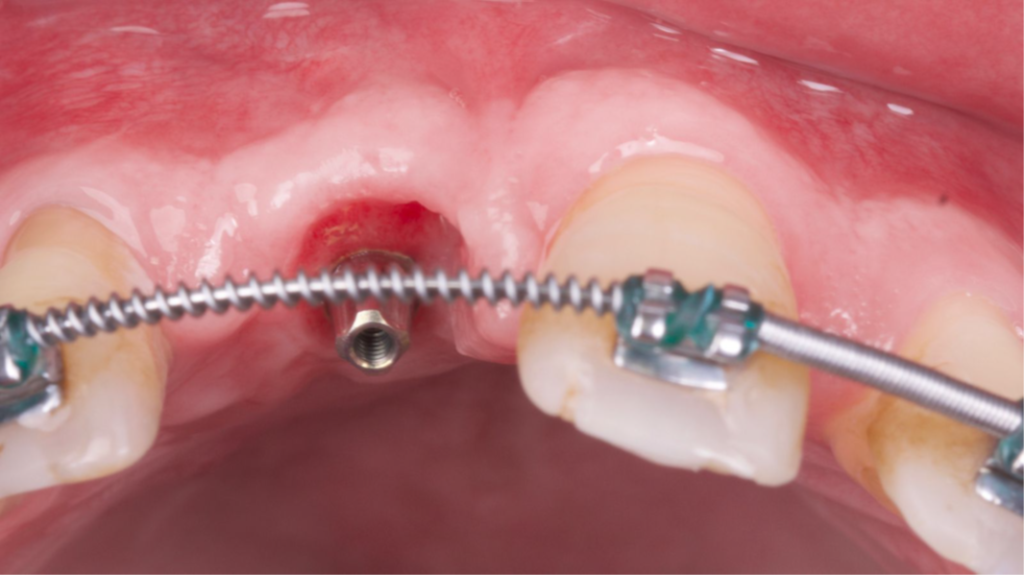

O tecido ósseo que suporta a estética rosa sofre diferentes modificações após uma extração e o biótipo gengival do paciente desempenha um papel importante na resolução multidisciplinar da instalação de um implante na zona estética. Uma alternativa viável de técnica para obter resultados estéticos e funcionais é a técnica VIP-CT (Vascularized Interpositional Periosteal Connective Tissue Flap).

Paciente do sexo masculino encaminhado pela Ortodontia para a instalação de um implante ao nível do dente 1.1 (Figura 1), com diastemas mésio-distais de 2mm, para utilização do implante como ancoragem absoluta e melhor andamento da movimentação ortodôntica.